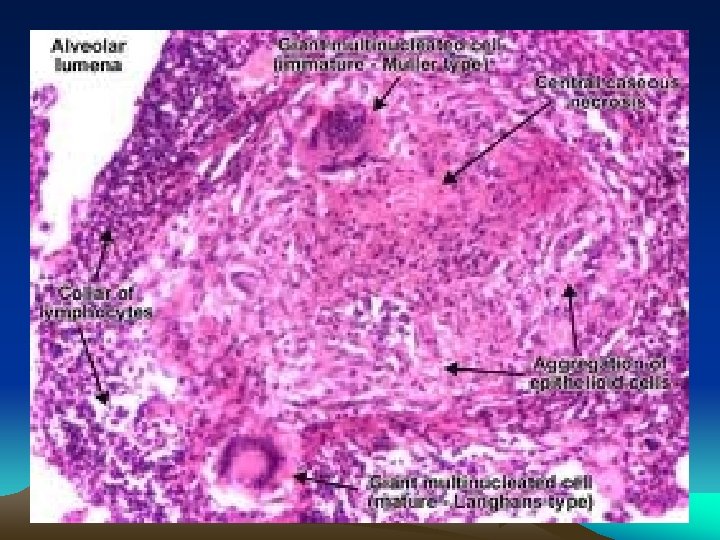

Histology : Epithelioid cell granulomas • epithelioid cells • lymphocytes • plasma cells • multinucleated langhan’s type giant cells • with or without central caseation

Granulomatous inflammation Granulomas are millimeter size nodules of chronic inflammatory cells that can be isolated or confluent. Granuloma formation is the result of dealing with indigestible substances or pathogens and walls them off The essential component are modified macrophages named epithelioid cell (because of shape). Epithelioid cells can form multinucleated giant cells. Epithelioid cells are surrounded by a collar of lymphocytes and occasionally plasma cells. Fibrous connective tissue often surrounds granulomas (remodeling of tissue) Areas within the granuloma can undergo necrosis (prototype: caseous necrosis in tuberculosis). Necrosis can lead to calcification or liquefaction and formation of a cavern if drained.

Morphology B – Secondary Tuberculosis : • Focus of consolidation, < 2 cm • Within 1 -2 cm of apical pleura • Histology : Caseating granulomas